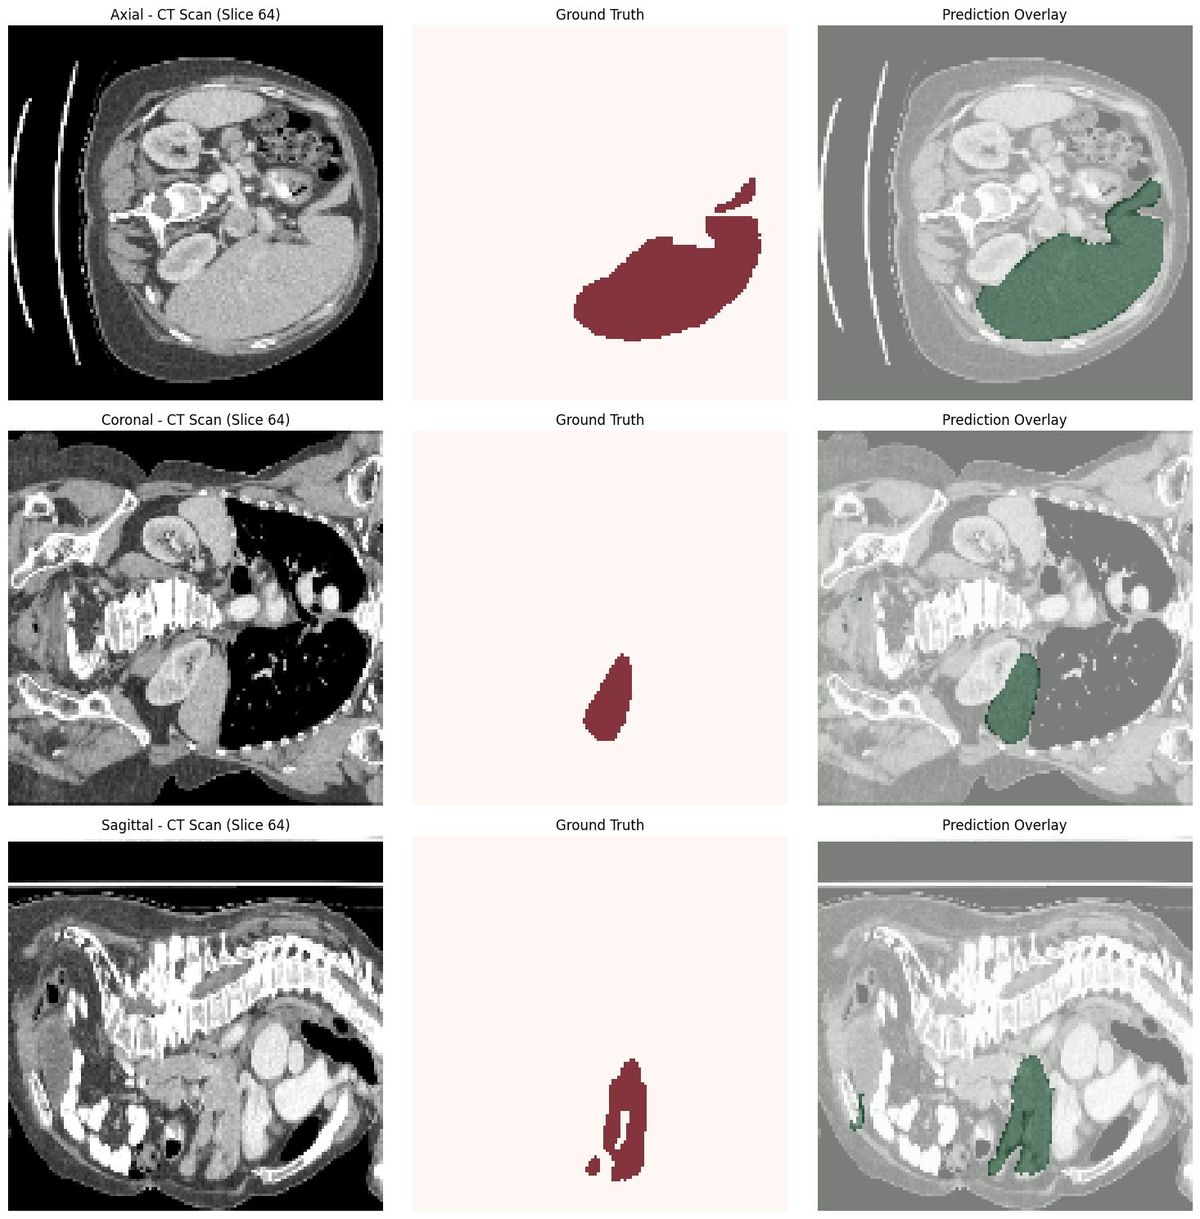

Training the model for ~160 epochs on my local RTX 3060 (12GB), and the system achieved a 95.6% Dice score.

3. Uses a 3D Vision Transformer (SwinUNETR) for segmentation

4. Handles inference using MONAI’s sliding-window engine and produces accurate 3D liver masks that can be downloaded as NIfTI files